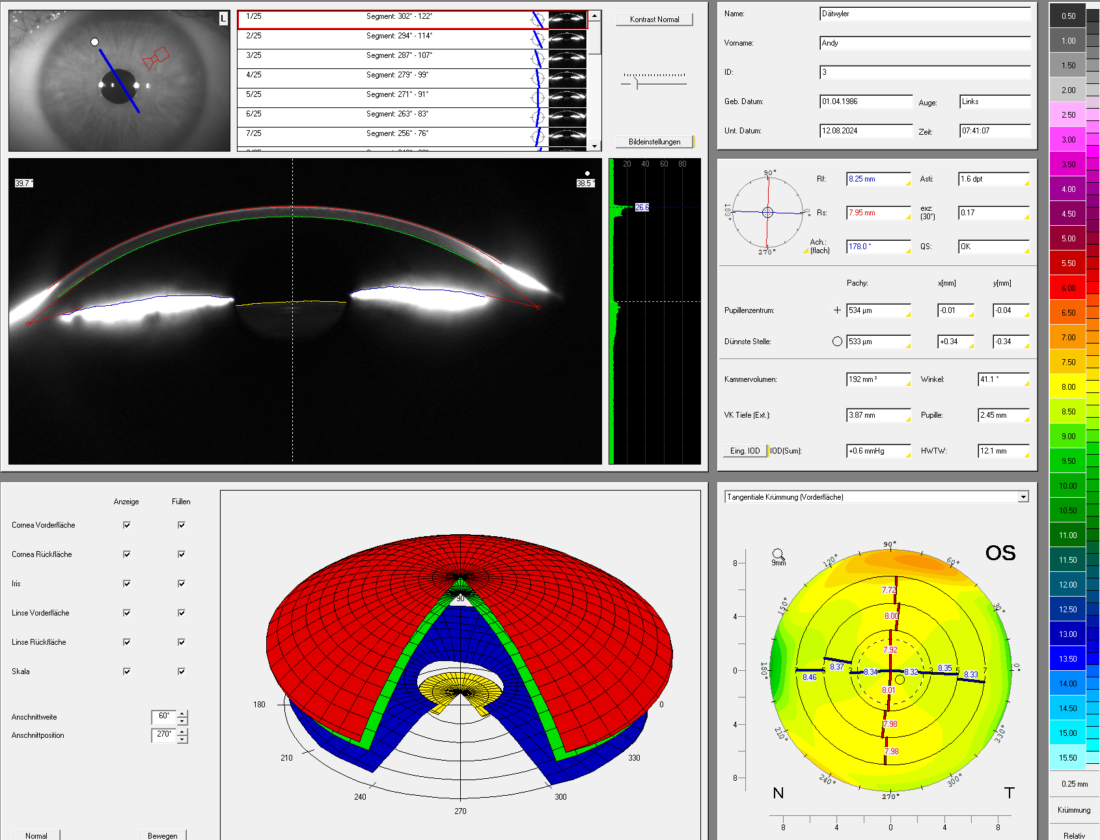

Der Augendruck alleine sagt nicht viel aus. Er muss im Zusammenhang mit der Gesamtsituation des Auges beurteilt werden, insbesondere mit der Erscheinung des Sehnerven (Netzhaut) und der Anatomie der vorderen Augenkammer.

Die Augen Vorsorge Untersuchung heisst bei uns „Panorama Check“, weil unter anderem mit einer Ultra-Weitwinkel Kamera die Netzhaut abgebildet wird. Dazu wird das Auge sorgfältig von vorne bis hinten angeschaut. Besonderer Fokus wird gelegt auf die Netzhaut mit dem Sehnerv und der Makula, aber auch die Augenlinse, die Vorderkammer, die für die Regulierung des Augendruckes wichtig ist. In der heutigen Zeit mit intensiver Bildschirmnutzung wird aber auch der Tränenfilm, die Schleimhaut und die Hornhaut kurz angeschaut. Zudem erfolgen Funktionsteste, um gröbere Auffälligkeiten in der Augenbeweglichkeit oder Pupillenreaktion festzustellen.

Der Augendruck ist also nur eines der Puzzleteile. Nachfolgend sehen Sie Aufnahmen wie sie bei uns im Rahmen eines „Panorama Check“ entstehen.